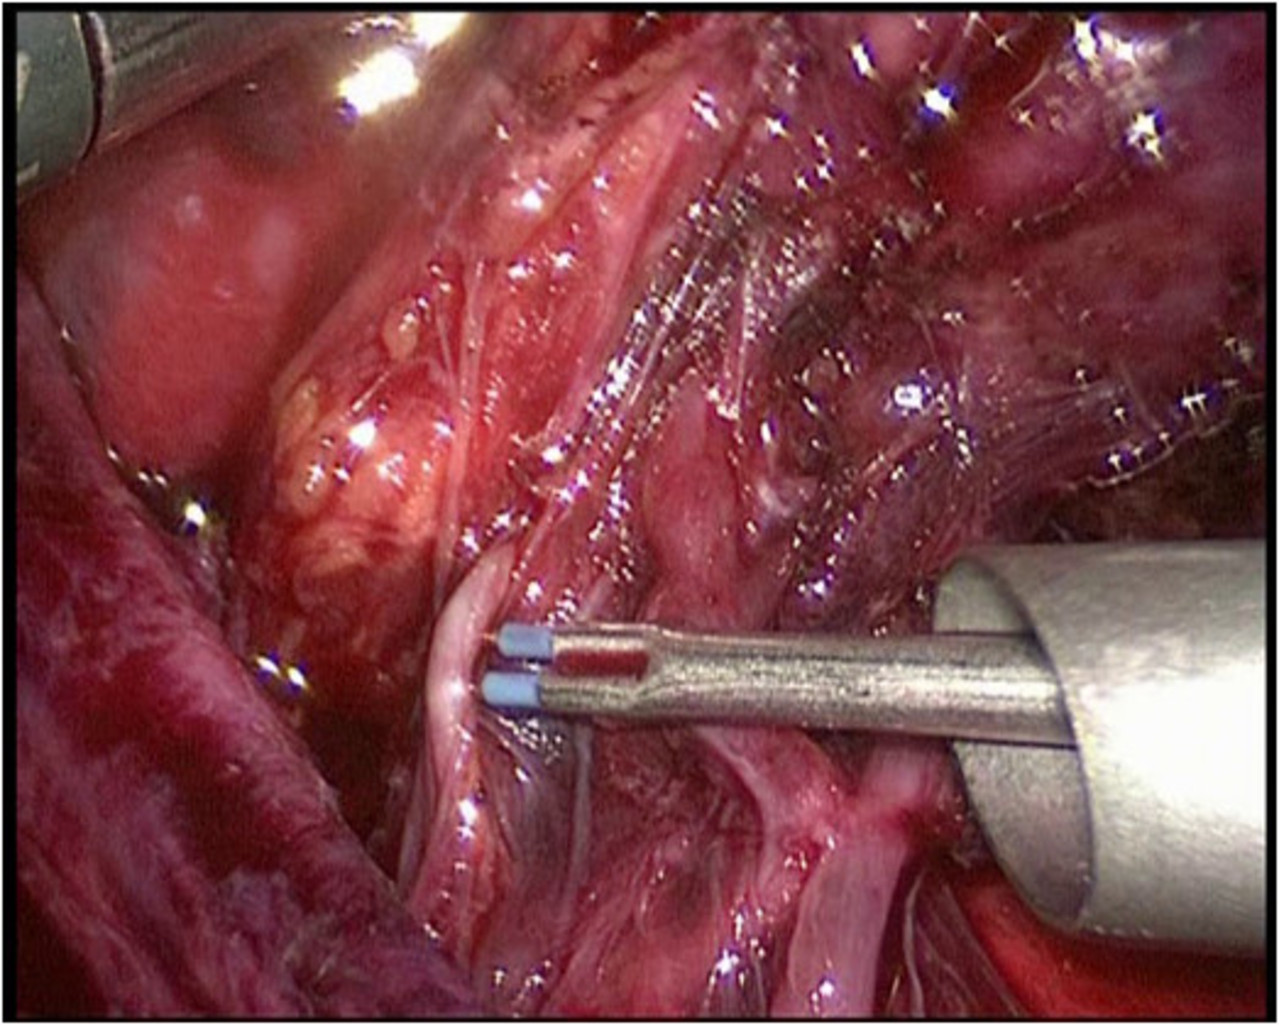

Minimal invasive Schilddrüsenoperation (ABBA):

Bei der von uns durchgeführten minimal invasiven Schilddrüsenoperationstechnik handelt es sich um die sog. „ABBA-Technik“ (Axillo-bilateral-breast-approach). Dabei wird die Schilddrüse durch einen ca. 2 cm langen Hautschnitt im Bereich der vorderen Achselhöhle sowie über 2 winzige Schnitte im Bereich der Brust (Randbereich der Brustwarze) operiert. Bei dieser Technik erfolgt die Präparation streng im Unterhautfettgewebe – Nerven, Gefäße oder die Brustdrüse werden dabei nicht tangiert. Ähnlich wie bei minimal invasiven Bauchoperationen wird das Operationsgebiet mit CO2-Gas gefüllt, um ausreichend Raum für die Einführung der feinen Operationsinstrumente zu erreichen. Die Schilddrüse wird dann unter Kamerasicht analog der herkömmlichen Operationstechnik operiert. Die Übersicht bei dieser Operation ist hervorragend; sämtliche Nerven- und Gefäßstrukturen können genau identifiziert werden. Ebenso werden die Stimmbandnerven mittels Neuromonitoring kontrolliert und die Nebenschilddrüsenkörperchen dargestellt und geschont.

Bösartige Schilddrüsentumore, Wiederholungseingriffe und stark vergrößerte Schilddrüsen sollten nach dem derzeitigen Erkenntnisstand noch herkömmlich operiert werden.